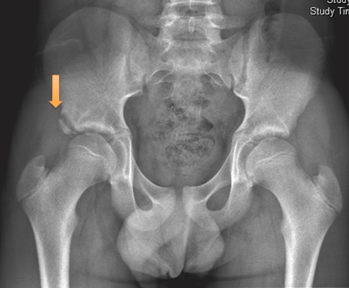

What could have caused this fracture?

AIIS avulsion fracture caused by the rectus femoris from forceful hip flexion